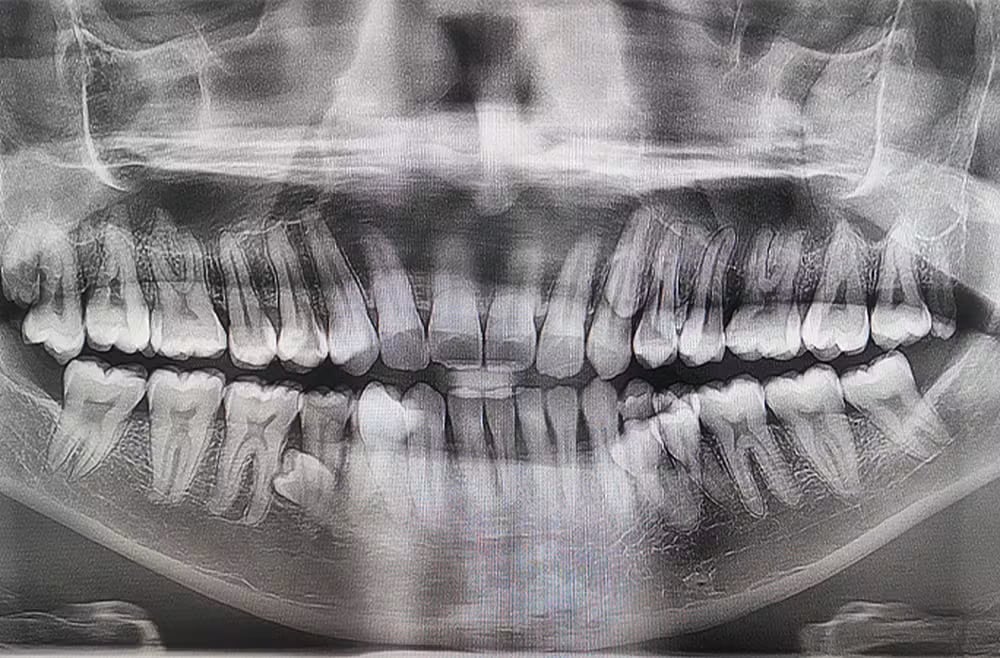

Posteriormente, un examen de rayos X permitió detectar cuatro dientes adicionales que aún no habían erupcionado, lo que elevó el total a 42 piezas dentales.

El Guinness World Records divulgó el caso este jueves 5 de marzo. Dentistas revisaron los estudios clínicos y confirmaron la cifra en 2023. Con ese proceso, el malasio obtuvo el título de hombre con mayor número de dientes en el mundo.